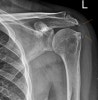

X-ray : 충돌증후군(Subacromial enthesophyte)

X-ray : 충돌증후군(Impingement syndrome)

상완골두와 견봉하 사이의 간격이 좁아진 것은(정상은 > 7mm) 오래된 회전근개 파열을 시사합니다.

Lateral view(=Scapular “Y” view) 또는 Neer view(=Supraspinatus Outlet view)는 견봉하 공간(subacromial space)을 보기에 용이합니다. 간혹 선천적으로 견봉이 굽어 이 공간을 작게 하거나(hooked type), 골극이 생겨 충돌을 일으키는 예가 있어 방사선 사진으로 이런 것들을 살펴봅니다.